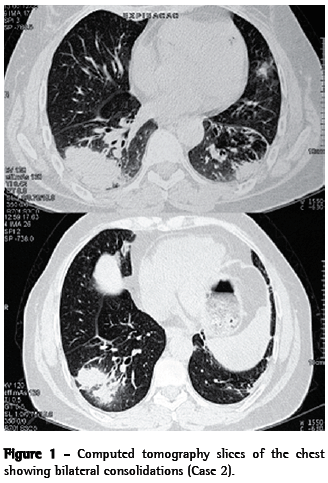

Case 2A 58-year-old female nonsmoker reported cough, moderate weight loss, fatigue and joint pain. The patient had a history of childhood asthma. After age 40, she experienced recurrence of the asthma-a fact that she attributed to contact with paints and solvents in the workplace. The patient used inhaled formoterol and budesonide (12/400 µg) daily, achieving satisfactory symptom control. A chest X-ray and a tomography scan of the chest showed bilateral consolidations and bronchiectasis in the lower lobes (Figure 1). Laboratory tests revealed the following: hematocrit, 41,1%; hemoglobin, 13.7 g/dL; leukocytes, 8,970, with lymphopenia (1,076 lymphocytes); ANF, present (1:160), with a dotted nuclear pattern; ESR, 56 mm/h; and C-reactive protein, 27.60 mg/L. At the time, Wegener's granulomatosis was suspected due to antineutrophil cytoplasmic antibody (ANCA) serum positivity. There was no upper airway involvement.

DiscussionHere, we have described two cases of KFD. The actual incidence of this disease is estimated to range from 0.5% to 5% of all cases of adenopathy analyzed histologically.(15) In a retrospective study of 1,724 lymph node biopsy samples, KFD was found in 36 cases.(16) Various infectious agents, such as Epstein-Barr virus, herpes virus 6, herpes virus 8, parvovirus B19, parainfluenza virus, Yersinia spp. and toxoplasma, have been proposed as antigenic stimuli.(1) In our report, both patients presented bilateral consolidations, consistent with an infectious or inflammatory process. Although no infectious germs were identified, it is possible that this was the antigenic stimulus for the development of KFD.